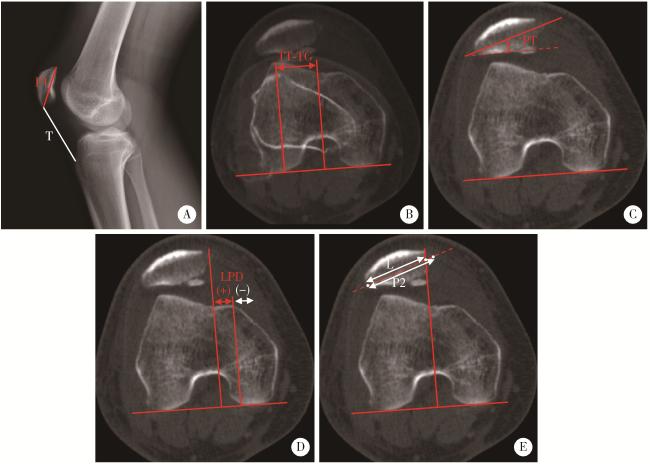

图3 侧位X线及轴位CT影像学指标的测量方法

Figure 3 Measurements of radiographic parameters on lateral plain radiographs and axial CT

A, Insall-Salvati index is the ratio of the patellar tendon length (T) to the patellar height (P1, distance from the superior pole to the inferior pole) on lateral plain radiographs; B, TT-TG distance is calculated by the transverse length between the trochlear groove and the tibial tuberosity on axial images; C, PT is the angle between the transverse axis of the patella and the posterior femoral condylar line; D, LPD describes the distance between the medial margin of the patella and the medial trochlear margin measured by lines perpendicular to the posterior femoral condylar line; E, bisect offset is determined by the ratio at which the patella width was bisected from its lateral aspect to the transverse width of the patella (L/P2). CT, computed tomography; LPD, lateral patellar displacement; PT, patellar tilt; TT-TG, tibial tubercle-trochlear groove.

术前常规拍摄膝关节侧位X线片和电子计算机断层扫描(computed tomography, CT)。评估Dejour分型以反映滑车发育不良程度(图 2),测量髌骨高度(Insall-Salvati指数)与胫骨结节-股骨滑车沟(tibial tubercle-trochlear groove,TT-TG)间距[18](图 3)。术后1周内摄轴位CT,比较术前和术后的髌骨倾斜角、髌骨外移距离和等分偏移率(bisect offset ratio,BSO)比值[19](图 3),评估髌股关节对位关系改善情况。